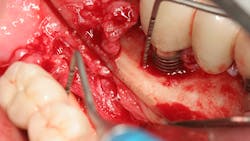

The expense and technical difficulty of removing an implant, rebuilding the defect, and replacing the failed dental implant with a new one can often be challenging. In addition, regenerative treatments for dental implant repair can be both costly and unpredictable if not done correctly (figures 1–3). Long-term maintenance and clinical oversight of peri-implant disease remains the most cost-effective and successful preventive measure for treating this disease.8 If this AI technology helps to determine the failure risk for the patient after surgical repair of the diseased dental implant, explantation with the replacement of a new implant or fixed/removable prosthesis may offer a better treatment alternative.